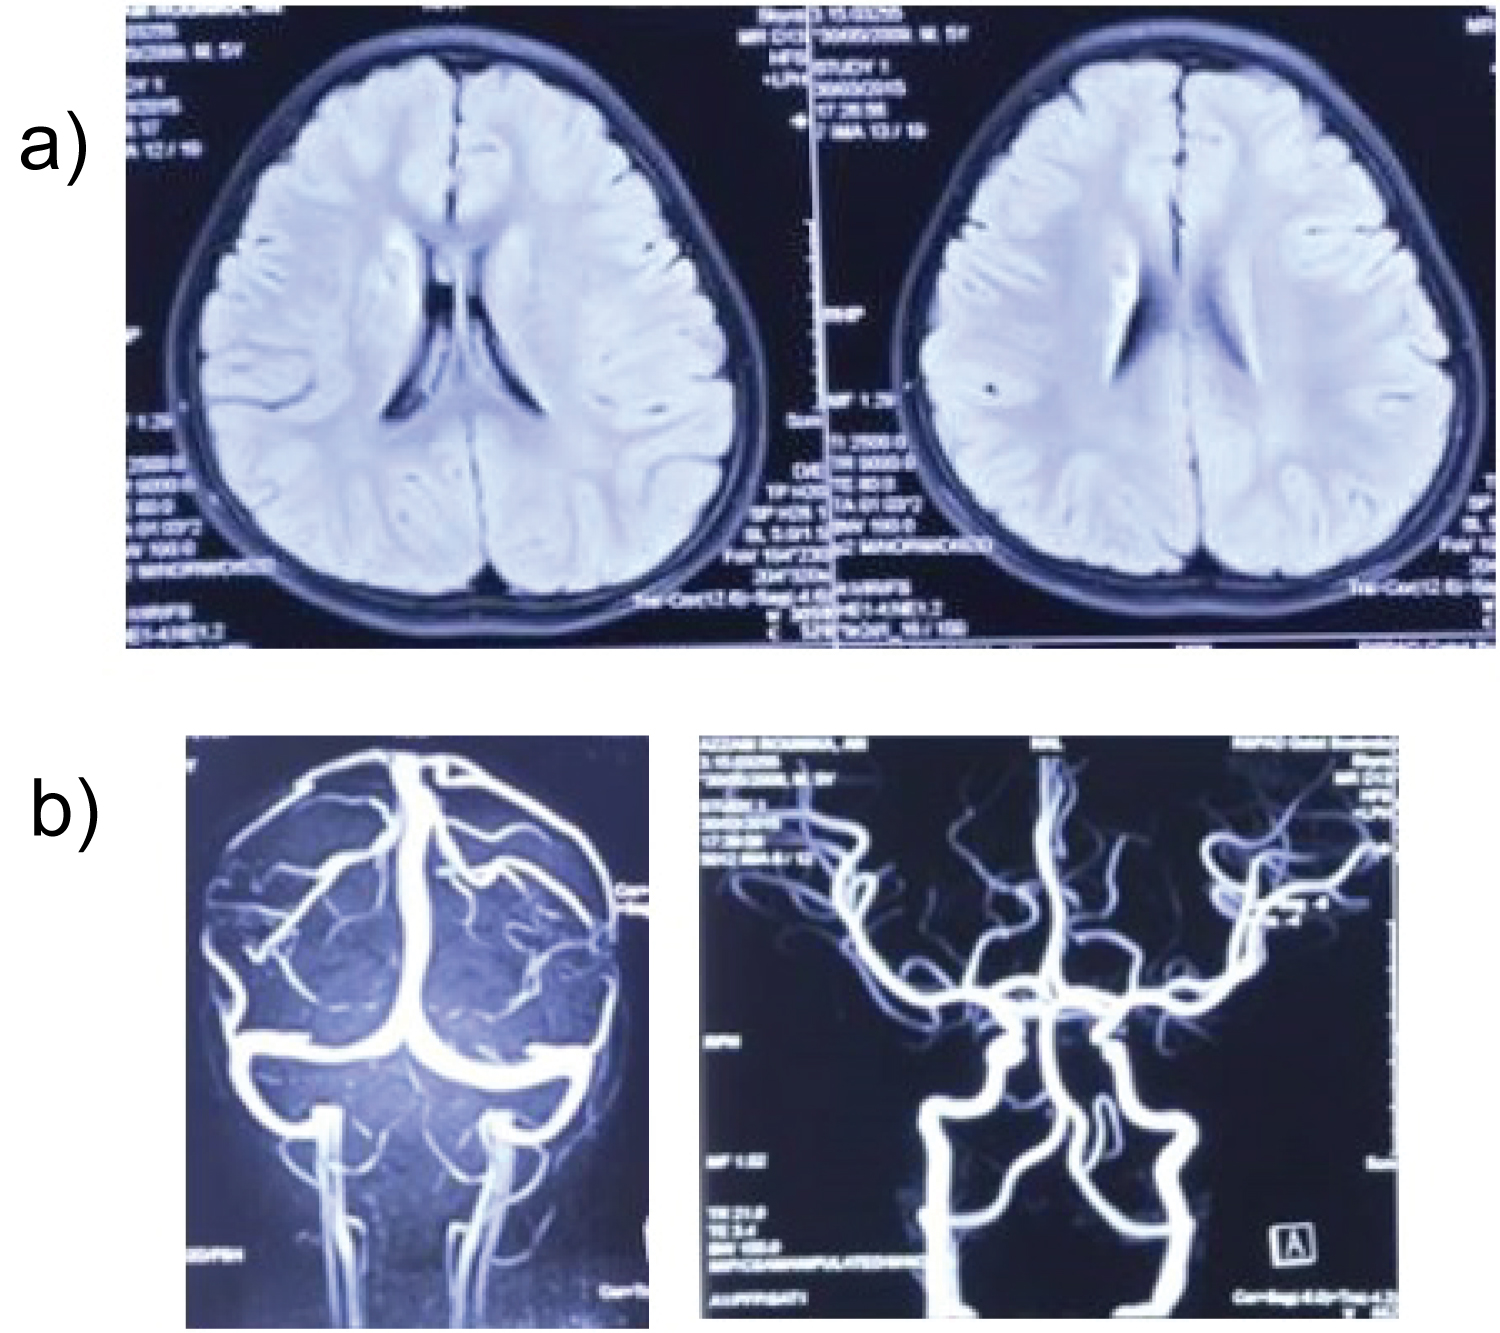

Whole brain MRI were found stenosis at left middle cerebral artery, left transverse sinus and left sigmoid sinus smaller than right transverse sinus and sigmoid sinus, and chronic infarct area are left parietal region.

These results were consulted to the interventional radiology department and IAHF procedure was performed. After IAHF, we found direct improvement in right side motor function, he can do rapid alternating movements even he still leaks of strength to grip. Result from IAHF procedure suggested an occlusion of left middle cerebral artery, collapse of left transverse and sigmoid sinus were release post flushing. No AVM, AV fistula, tumor even extravasation of contrast (Figure 2 and Figure 3).

Figure 2: Brain MR Imaging pre IAHF. View Figure 2